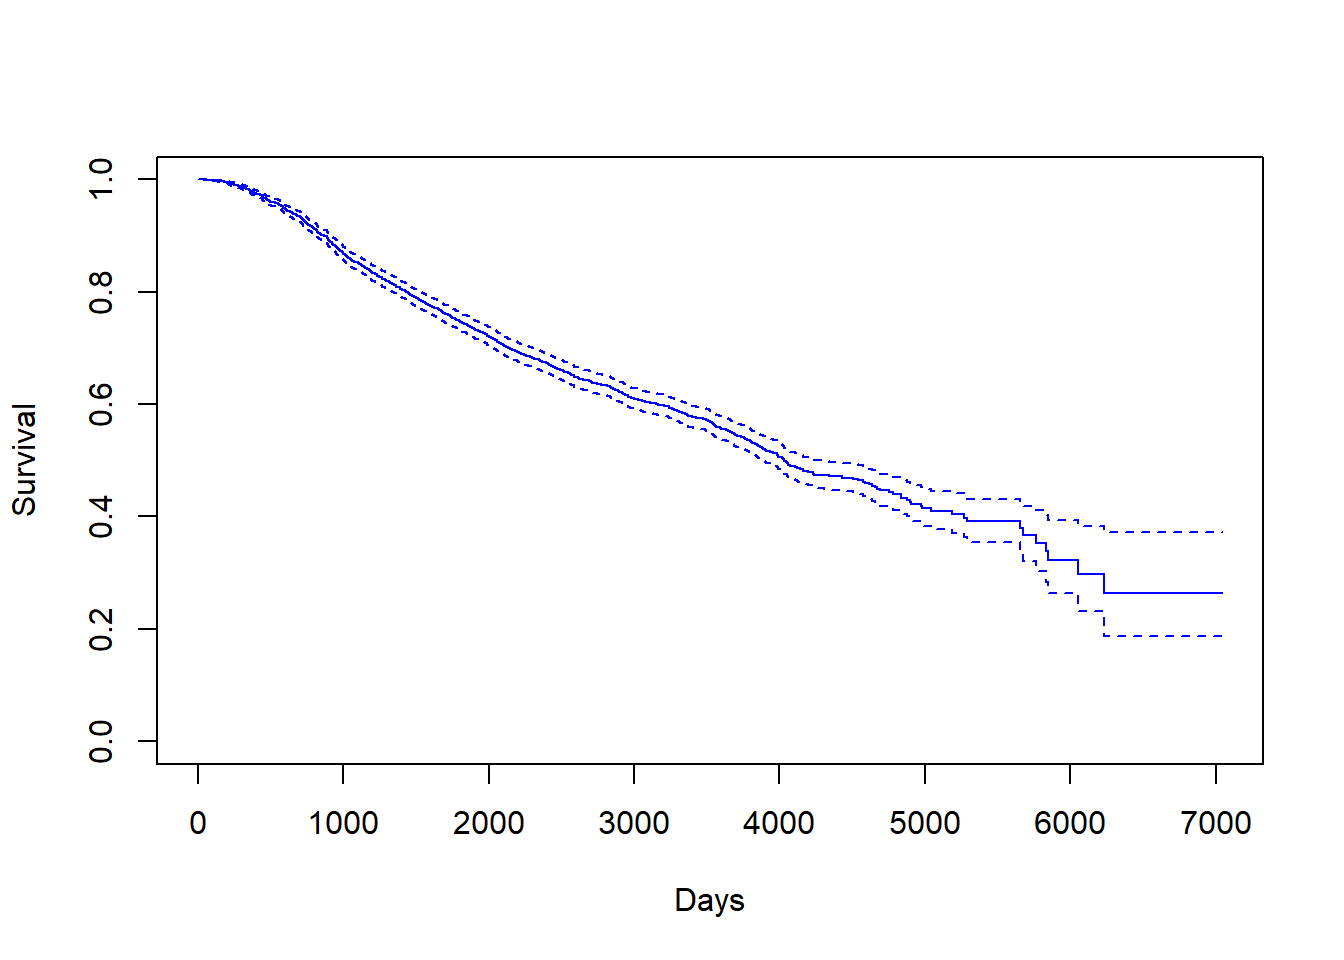

From the founding date, how long does it take an average company to go public through an IPO? What characteristics of the company are associated with this duration of time? With survival parametric models and Cox proportional hazards models, we will shed light on companies’ time to IPO in relationship with their profitability, size, sector and leadership, using Kaggle’s IPO data up until 1/1/2018. Familiar probability and statistical concepts will prove useful in our discovery and analysis, and the beauty of survival analysis will be unveiled.

How do differing breast cancer treatments compare in effectiveness? When considering which treatment is best, we would expect for more invasive procedures to lead to greater survival outcomes, but is this truly the case? Using data from the Netherland Cancer Institute, we were able to analyze survival outcomes across different treatments. In this analysis we compare outcomes for patients who underwent chemotherapy, hormonal, and amputation treatments and determine if any of the treatments leads to longer survival time compared to others.

Cancer has become a critical health problem. Among all sorts of cancer, breast cancer is the second common one in American women. Motivated by providing statistical insight into this disease, my teammate and I analyzed breast cancer data from Rotterdam Tumor Bank. This analysis aimed to investigate potential key factors affecting the survival time of breast cancer patients and also promote the awareness of breast cancer screening.

Factors that Affect Breast Cancer Survival — A Survival Analysis with Rotterdam Dataset

According to World Health Organization, Cancer is a leading cause of death worldwide, accounting for an estimated 9.6 million deaths in 2018. And amongst all cancer types, breast cancer(along with lung cancer) has the top cases of death: 2.09 million cases in 2018. According to the CDC, Breast cancer is also the second most common cancer among women in the United States, comprising 22.9% of invasive cancers in women and 16% of all female cancers. We think it would be interesting to take a look at survival and many related statistics of breast cancer.